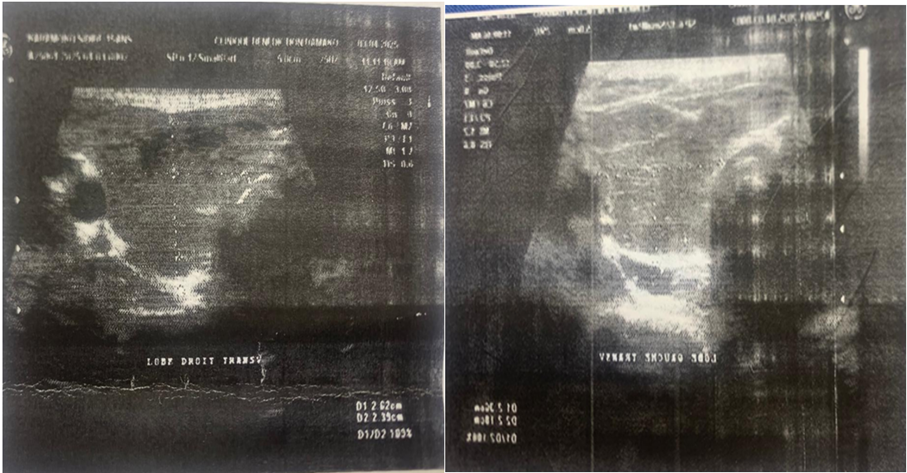

Figure 2: Thyroid ultrasound of the patient (As a clue by the arrows, 2 very vascularized isthmic nodules ; on a heterogeneous and hypervascularized goiter).

Cervical ultrasound (Figure 2) revealed the following :

- An enlarged right lobe, echogenic, heterogeneous, and measuring 50x26x21mm

- An enlarged left lobe, measuring 50x26x23mm, echogenic and heterogeneous

- Isthmic hypertrophy (11mm thick), grossly echogenic, heterogeneous, and presenting two nodules measuring 07x06mm and 07x04mm

- No cervical lymphadenopathy, and the jugulocarotid bundles appeared normal

- On color Doppler, diffuse and perinodular hypervascularization of the thyroid gland related to thyroid overactivity